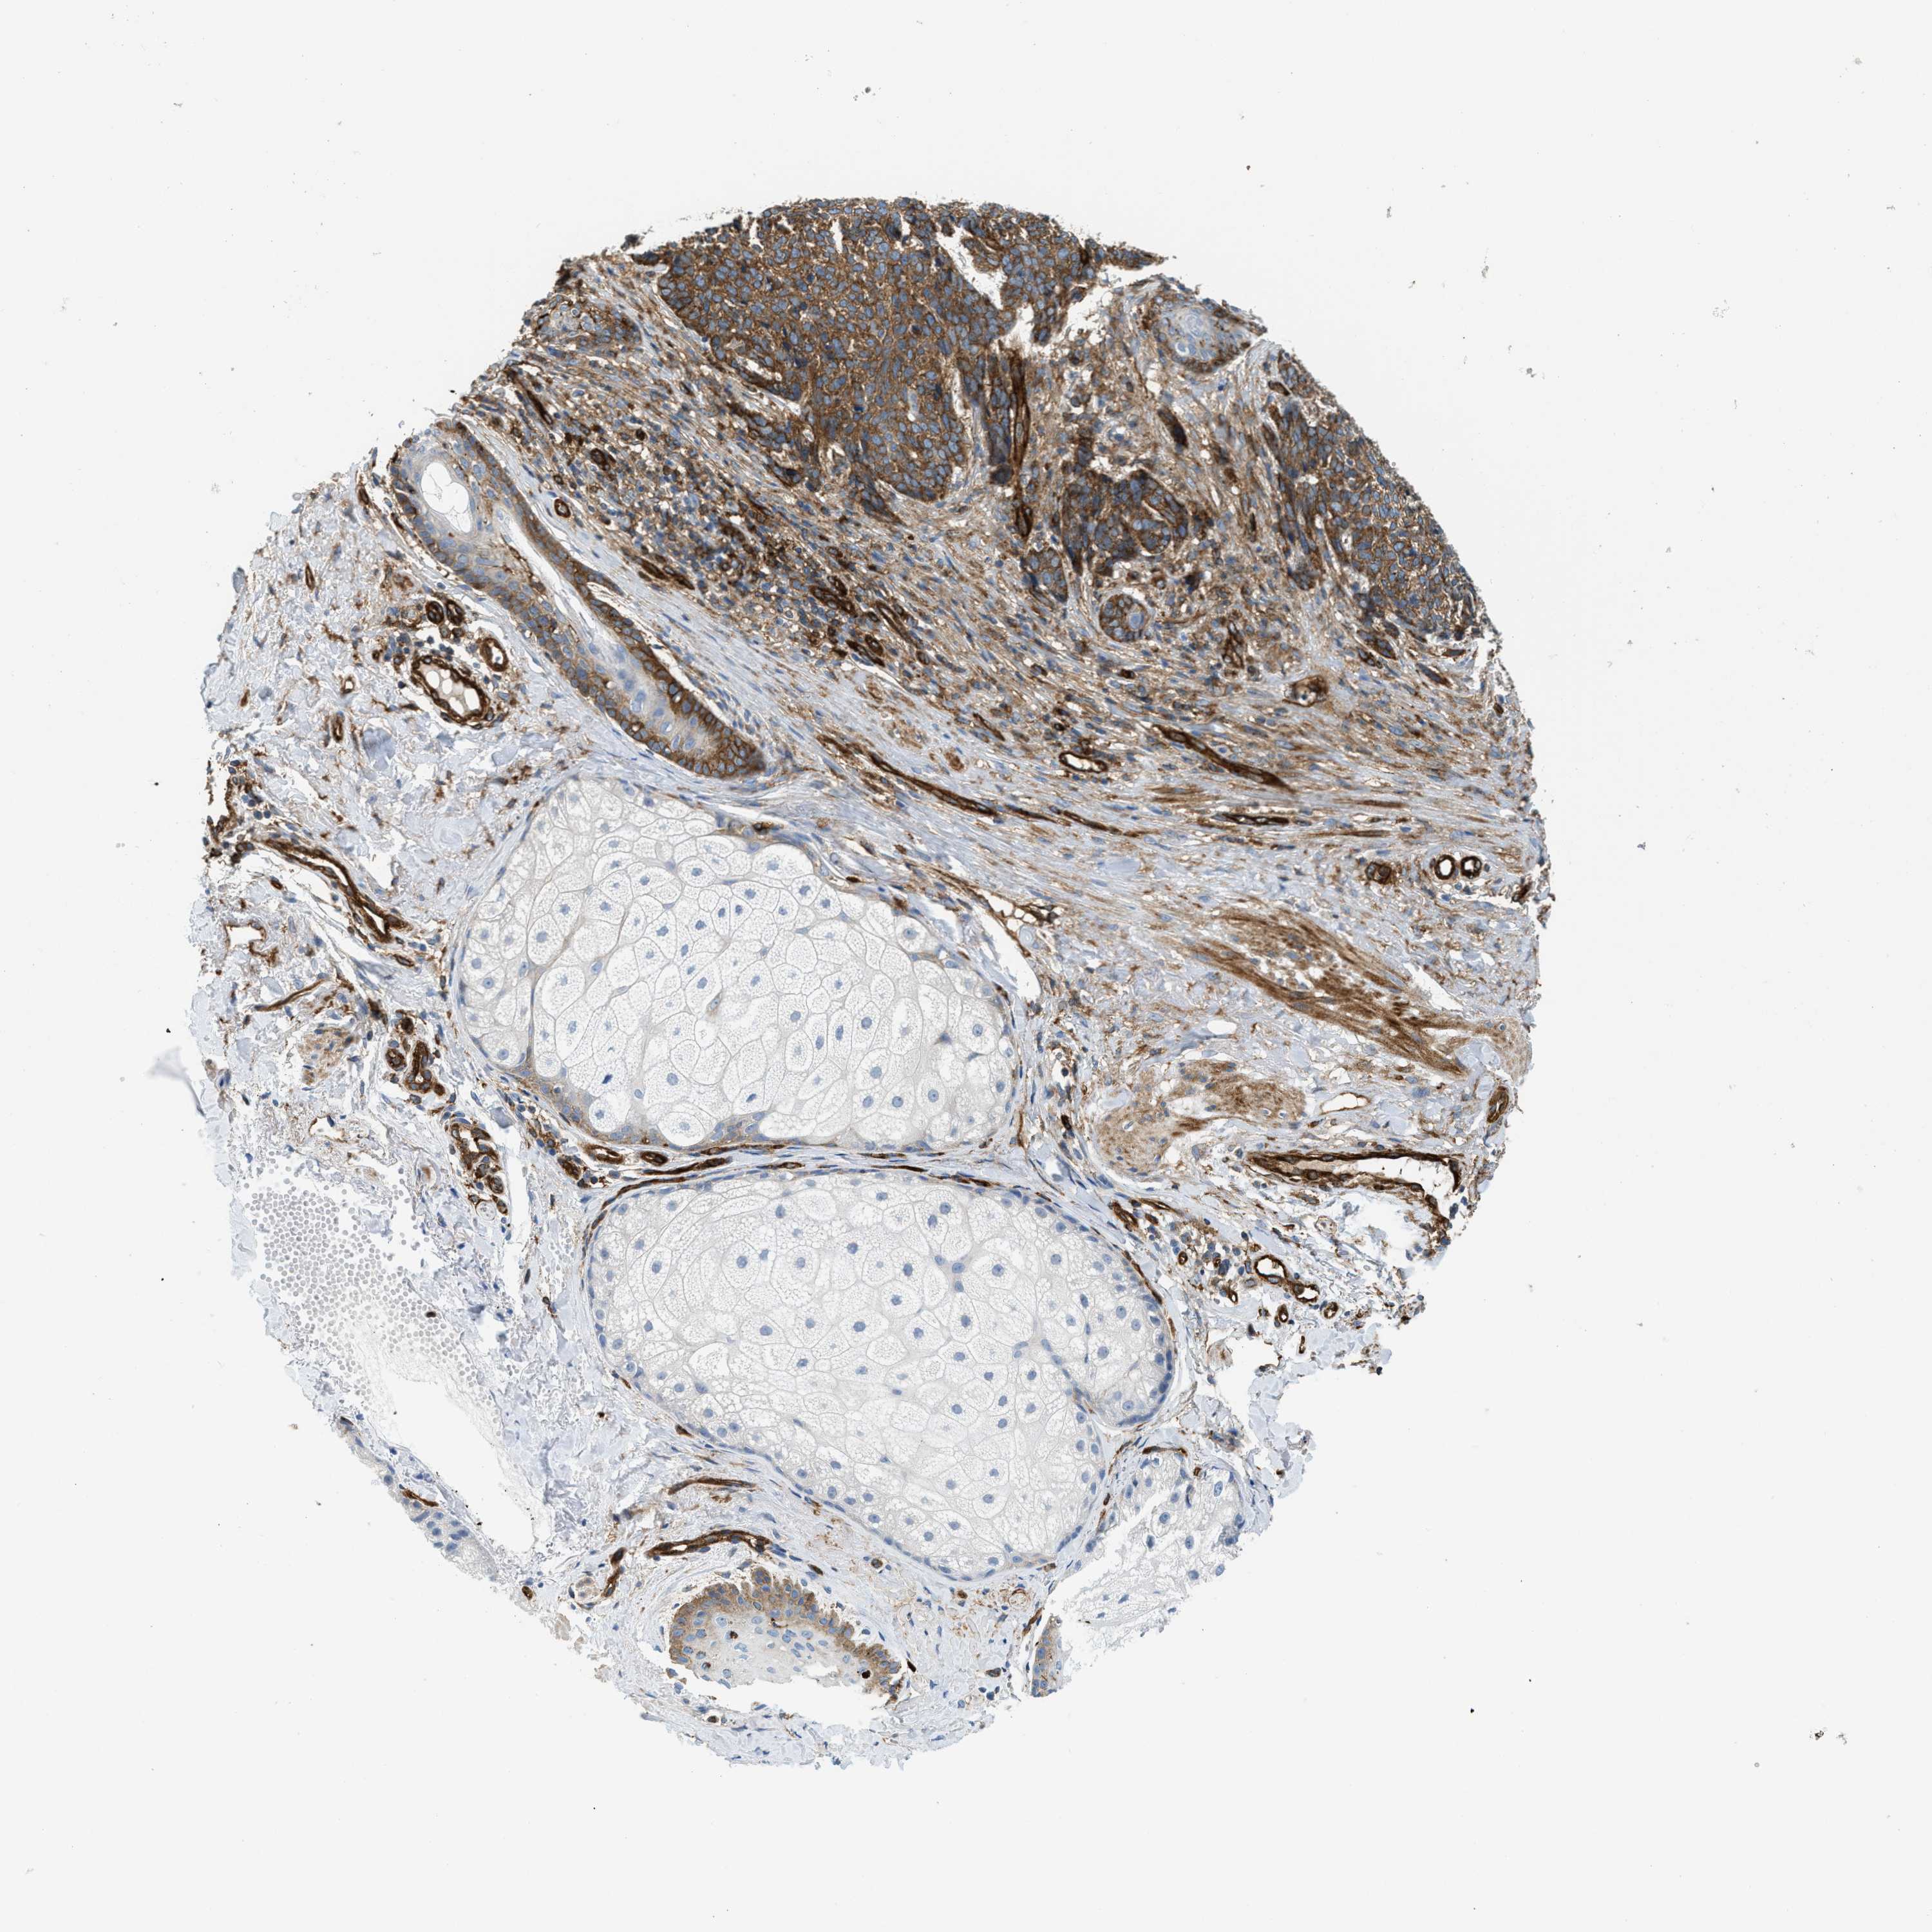

SKIN CANCER - Protein expressioni

A mouse-over function shows sample information and annotation data. Click on an image to view it in a full screen mode. Samples can be filtered based on level of antibody staining by selecting one or several of the following categories: high, medium, low and not detected. The assay and annotation is described here.

Each image is clickable and will lead to virtual microscopy that enables deeper exploration of all samples and also displays staining intensity scores, fraction scores and subcellular localization as well as patient and tissue information for each sample.

Antibody HPA013606

Staining

High

Medium

Low

Not detected

Intensity

Strong

Moderate

Weak

Negative

Quantity

>75%

75%-25%

<25%

None

Location

Nuclear

Cytoplasmic/membranous

Cytoplasmic/membranous,nuclear

Squamous cell carcinoma in situ, NOS

Squamous cell carcinoma, NOS

Squamous cell carcinoma, metastatic, NOS

Basal cell carcinoma

Adnexal tumor, benign